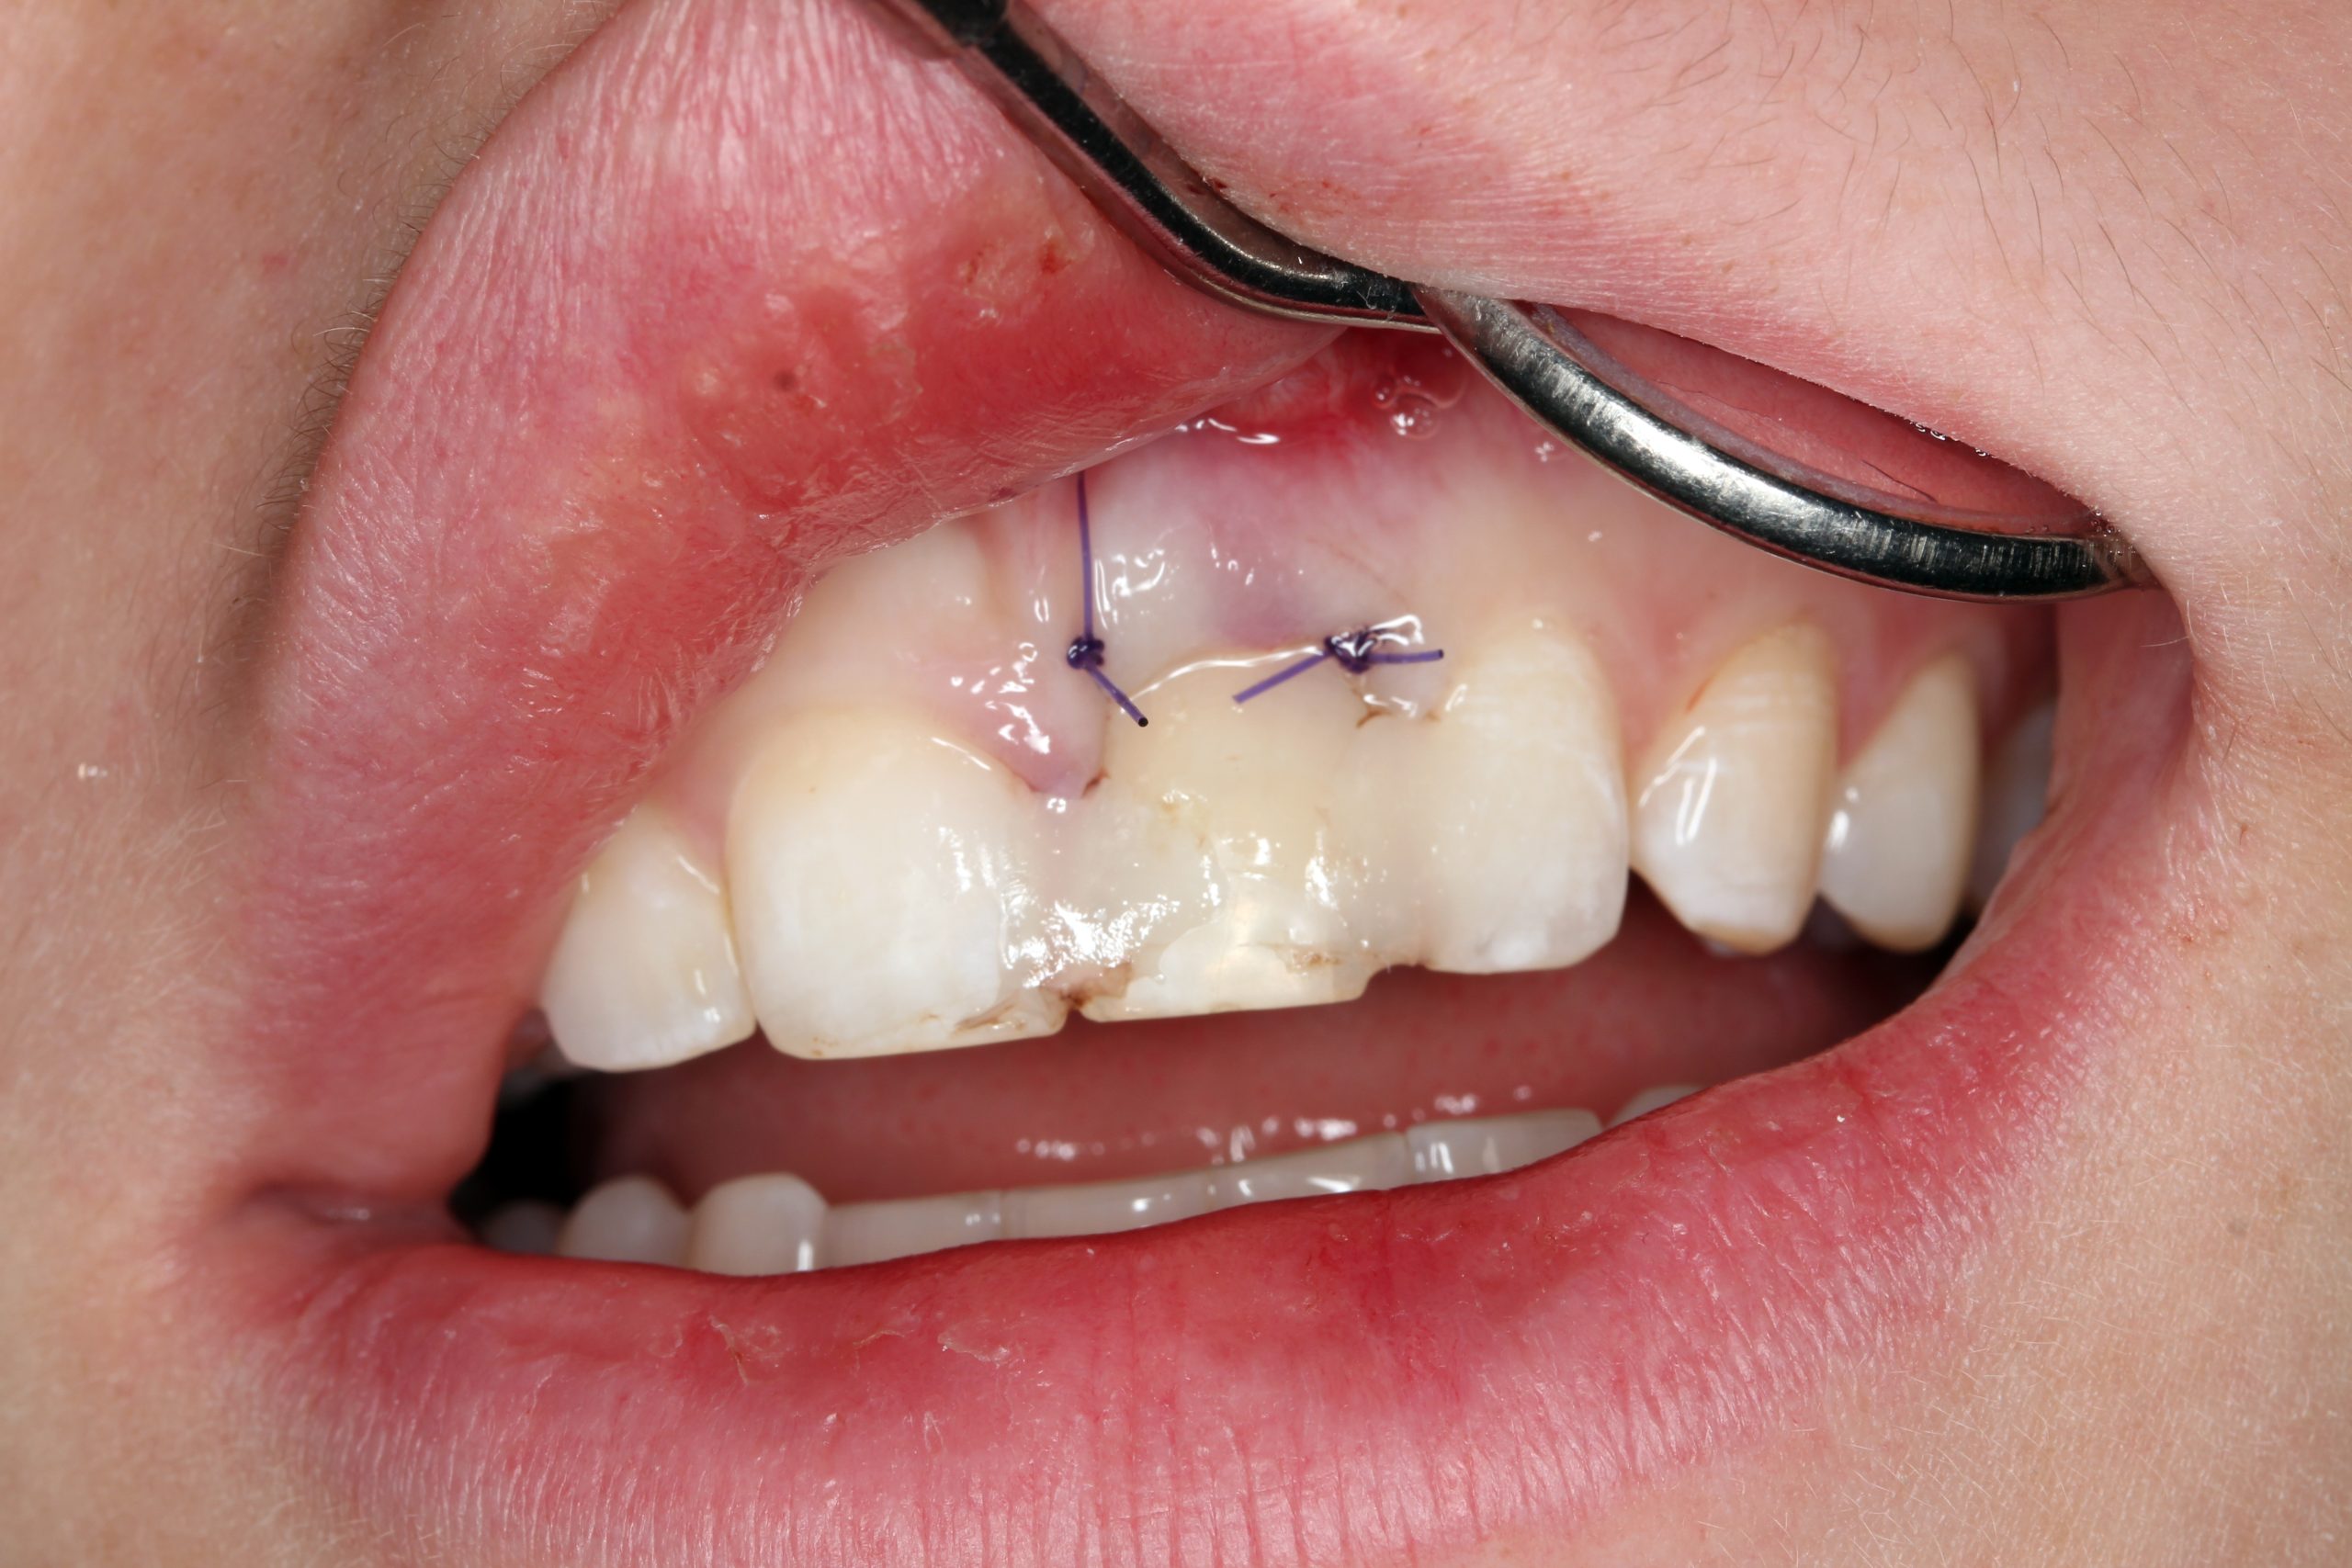

Nach der Extraktion und Exkochleation wurde die Extraktionswunde revidiert. Die vestibuläre Wand der Alveole war bis auf den apikalen Teil erhalten. Das Zahnbett wurde nur mit einem antibiotikahaltigen Kollagenkegel aufgefüllt.

Der extrahierte Zahn diente als Provisorium. Die Wurzel wurde etwa 2 mm unterhalb der SZG abgeschnitten, sodass dieser Teil im Weichgewebe eingebettet war. Die Krone wurde mit Komposit an den Nachbarzähnen befestigt.